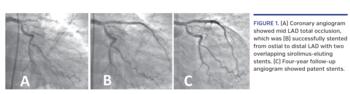

54-year-old, non-diabetic, normotensive, non-smoker male presented with acute anterior-wall myocardial infarction (AWMI) at the emergency room in August 2007. He underwent primary angioplasty of an occluded proximal left anterior descending (LAD) (Figure 1A), and two overlapping 2.75 x 23 mm and 2.5 x 33 mm Cypher stents (Cordis Corporation) were deployed from ostial to distal LAD (Figure 1B). Intravascular imaging was not performed during the percutaneous coronary intervention (PCI). A follow-up angiogram after 4 years showed patent LAD stents (Figure 1C). In August 2018 (11 years after PCI), he again presented with acute AWMI despite continued dual-antiplatelet therapy. Coronary angiography revealed total occlusion of the proximal LAD (Figure 2A). The lesion was crossed with a Choice PT coronary guidewire (Boston Scientific) and sequentially dilated with 1.25 x 15 mm and 2.5 x 15 mm balloons (Figure 2B). Intravascular ultrasound revealed mild neointimal hyperplasia in the proximal-mid LAD and a markedly under-expanded and malapposed stent throughout its length from ostial to distal LAD (Figure 3; Video 1). The mean luminal diameter (MLD) and mean vessel diameter (MVD) of the proximal LAD (2.31 mm vs 4.14 mm) and distal LAD (2.10 mm vs 3.55 mm) showed a gross mismatch suggestive of malapposition (Figure 3). The entire stented segment was dilated with a 3.5 x 15 mm non-compliant balloon and the ostial-proximal LAD was additionally dilated with a 4 x 12 mm non-compliant balloon. TIMI-3 flow was achieved in the LAD (Figure 2C). Repeat IVUS revealed well-apposed stent struts, with mean cross-sectional area of 9.50 mm2 and MLD of 3.65 mm in the proximal LAD and cross-sectional area of 7.02 mm2 and MLD of 3.10 mm in the distal LAD (Figure 4; Video 2). As the result was optimal, no additional stent was deployed across the LAD. Patient was discharged on dual-antiplatelet therapy and was asymptomatic at 3-month follow-up exam.